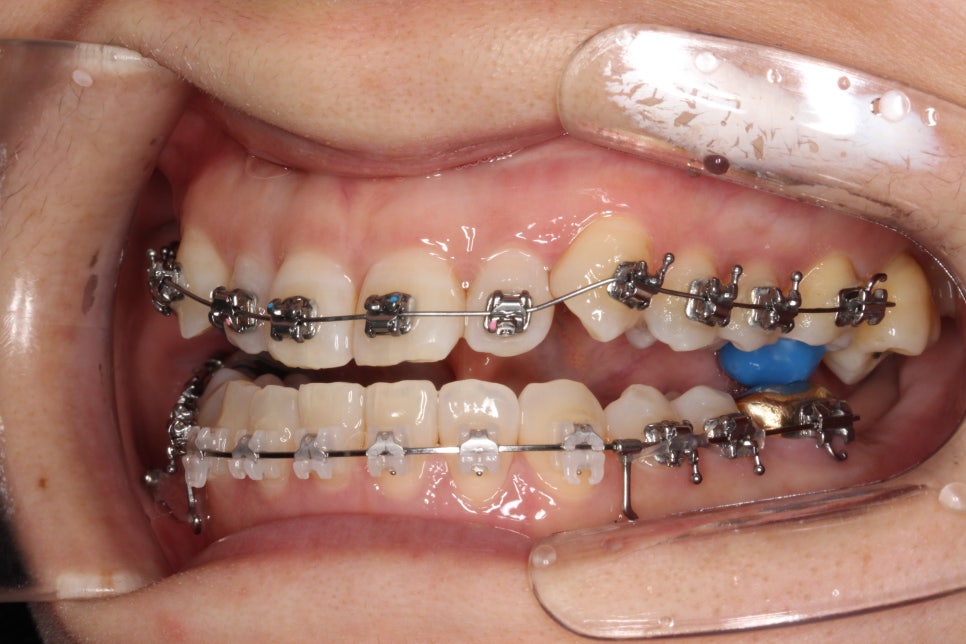

치료 초기 단계

치료를 시작한지 얼마 되지 않았을 때의 모습입니다. 아래쪽은 미니스크류를 식립하여 당기고 있고, 앞니가 넘어올 수 있게 어금니에 #바이트블록을 올렸습니다. 밥먹을 때 힘드셨을 겁니다 ㅠ